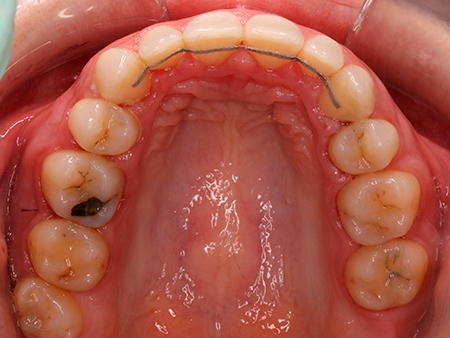

Ortodoncia con brackets linguales Incognito

Después de analizar su caso, nuestras ortodoncistas le recomendaron abordar un tratamiento de ortodoncia con brackets linguales Incognito. Su objetivo era corregir la sobremordida, el apiñamiento y la mordida en tijera que Mireia presentaba en un inicio.

Tras un tratamiento de ortodoncia con brackets Incognito de 18 meses de duración, Mireia goza de una oclusión óptima y, además, ya disfruta de la sonrisa que siempre había deseado.